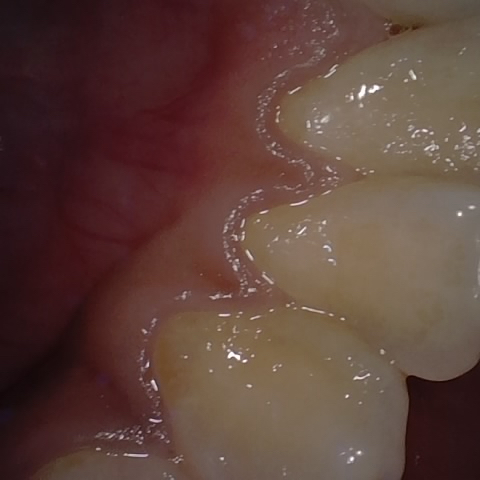

NHD38251

Annotated as "Good"